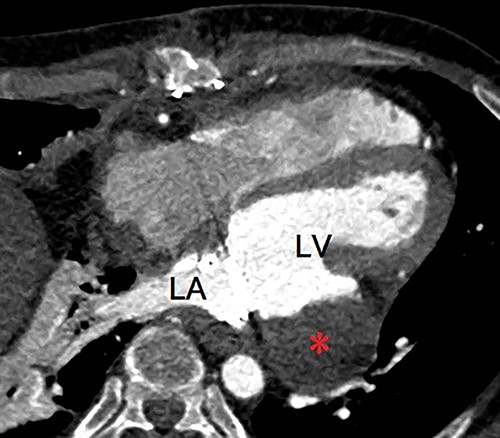

A 40-year-old man was referred to our hospital with suspected LVPA without any symptoms. He had a three-time history of mitral valve surgery, all of which due to infectious endocarditis (IE). Initial mitral valve repair was performed 8 years ago, and MVR were performed 7 years and 4 years ago. In addition, he had a history of severe atopic dermatitis. He had experienced another episode of IE 1 year ago, which was treated with antibiotic therapy. Enhanced computed tomography (eCT) at that time revealed a small nodular contrast region immediately below the mitral valve annulus in the left ventricular muscle. However, the evaluation could not clearly indicate an aneurysm at that point. Transthoracic echography (TTE) at our hospital revealed an LVPA that gradually expanded at the posterior wall immediately below the mitral valve annulus, and the mechanical prosthetic valve had normal function. eCT revealed a massive LVPA that was >50 mm in size (Fig. 1). We decided to close the LVPA due to a risk of future rupture. Thus, the patient underwent his fourth median sternotomy, through which a cardiopulmonary bypass was established with ascending aortic cannulation and bicaval drainage, and the heart was arrested with antegrade cardioplegia. The mitral prosthetic valve was visualized through a right-sided left atriotomy. After removing the valve, the orifice of the aneurysm was confirmed (Fig. 2). Unlike that in the case of active IE, the tissue around the aneurysm was not vulnerable; thus, the orifice was closed using a bovine pericardial patch (Fig. 3A). In addition, BioGlue (CryoLife Inc., Kennesaw, GA, USA) was injected into the aneurysm (Fig. 3B). The aneurysm was filled with BioGlue to prevent blood flowing into it. Thereafter, MVR was performed using a 25-mm On-X heart valve (CryoLife Inc., Kennesaw, GA, USA). Postoperative eCT revealed complete closure of the aneurysm (Fig. 4). The patient’s cardiac function was good, and no paravalvular leakage was observed on TTE. He was discharged home without complications. At the 10-month follow-up, the size of the aneurysm found to be reduced, as revealed using TTE.

Postoperative enhanced computed tomography showing absent flow into the pseudoaneurysm (asterisk). LA, left atrium; LV, left ventricle.

Enhanced computed tomography showing a left ventricular pseudoaneurysm (arrow) just below the mitral valve annulus. LA, left atrium; LV, left ventricle.